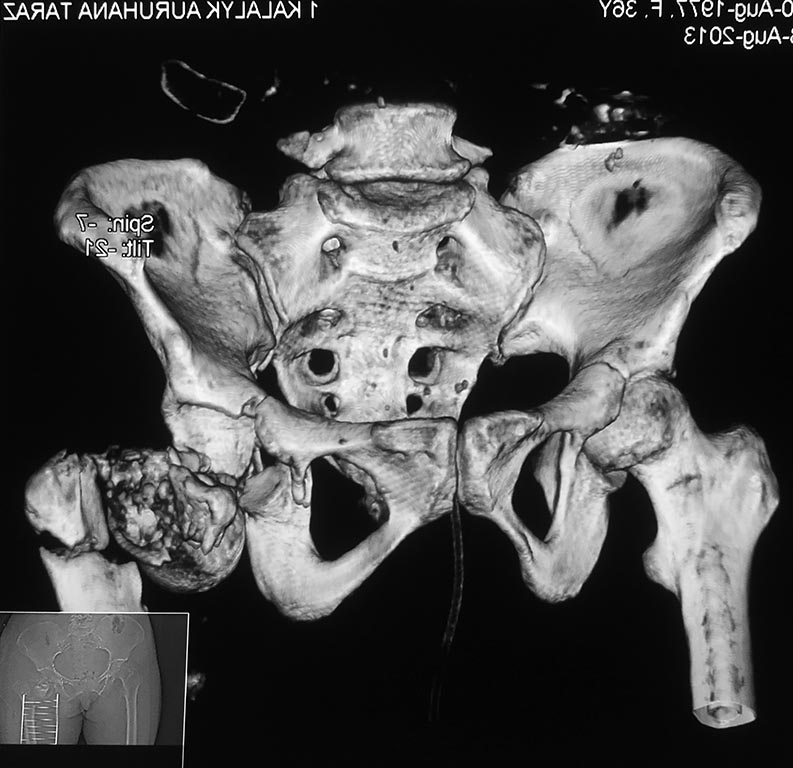

Открытый перелом бедра и вертлужной впадины

больная 1977г.р. открытый перелом оскольчатый проксимального отдела левого бедра со смещением, перелом дна вертлужной впадины с той же стороны. Находится на вытяжении. рана в ягодичной области, гранулирует. травма 14.08.13г.